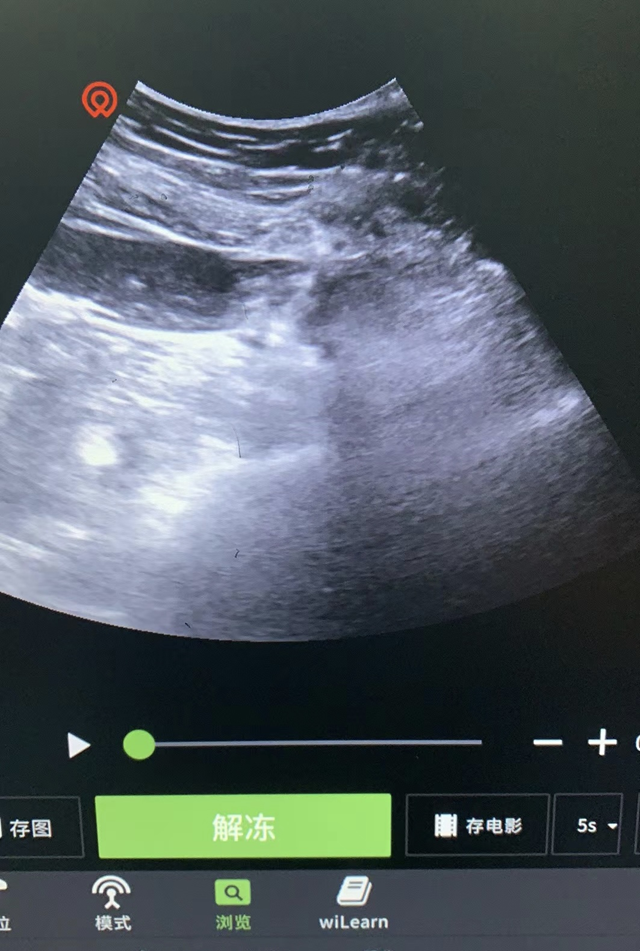

综合李嬢嬢具体情况,徐力建议采用腰交感神经射频调理的治疗方法,李嬢嬢也欣然同意。一切术前准备就绪后,徐力将一根直径0.7毫米的射频针在超声引导下穿刺到李嬢嬢腰大肌深面,在腰2椎体层面找到腰交感神经节进行射频治疗。